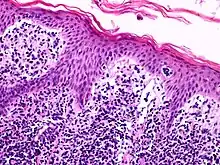

![]() A histological view of Lutzner cells surrounded by erythrocytes in a blood smear. | |